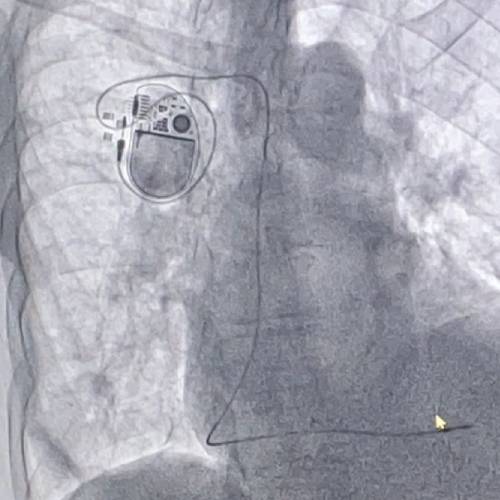

¿Qué es el implante de marcapaso definitivo?

A través de sus circuitos eléctricos y los catéteres “monitorea” permanentemente el ritmo cardíaco espontáneo del paciente y cuando éste desciende por debajo de la frecuencia programada, emite un estímulo eléctrico que provoca un latido cardíaco evitando de esta manera, que la frecuencia cardiaca caiga.